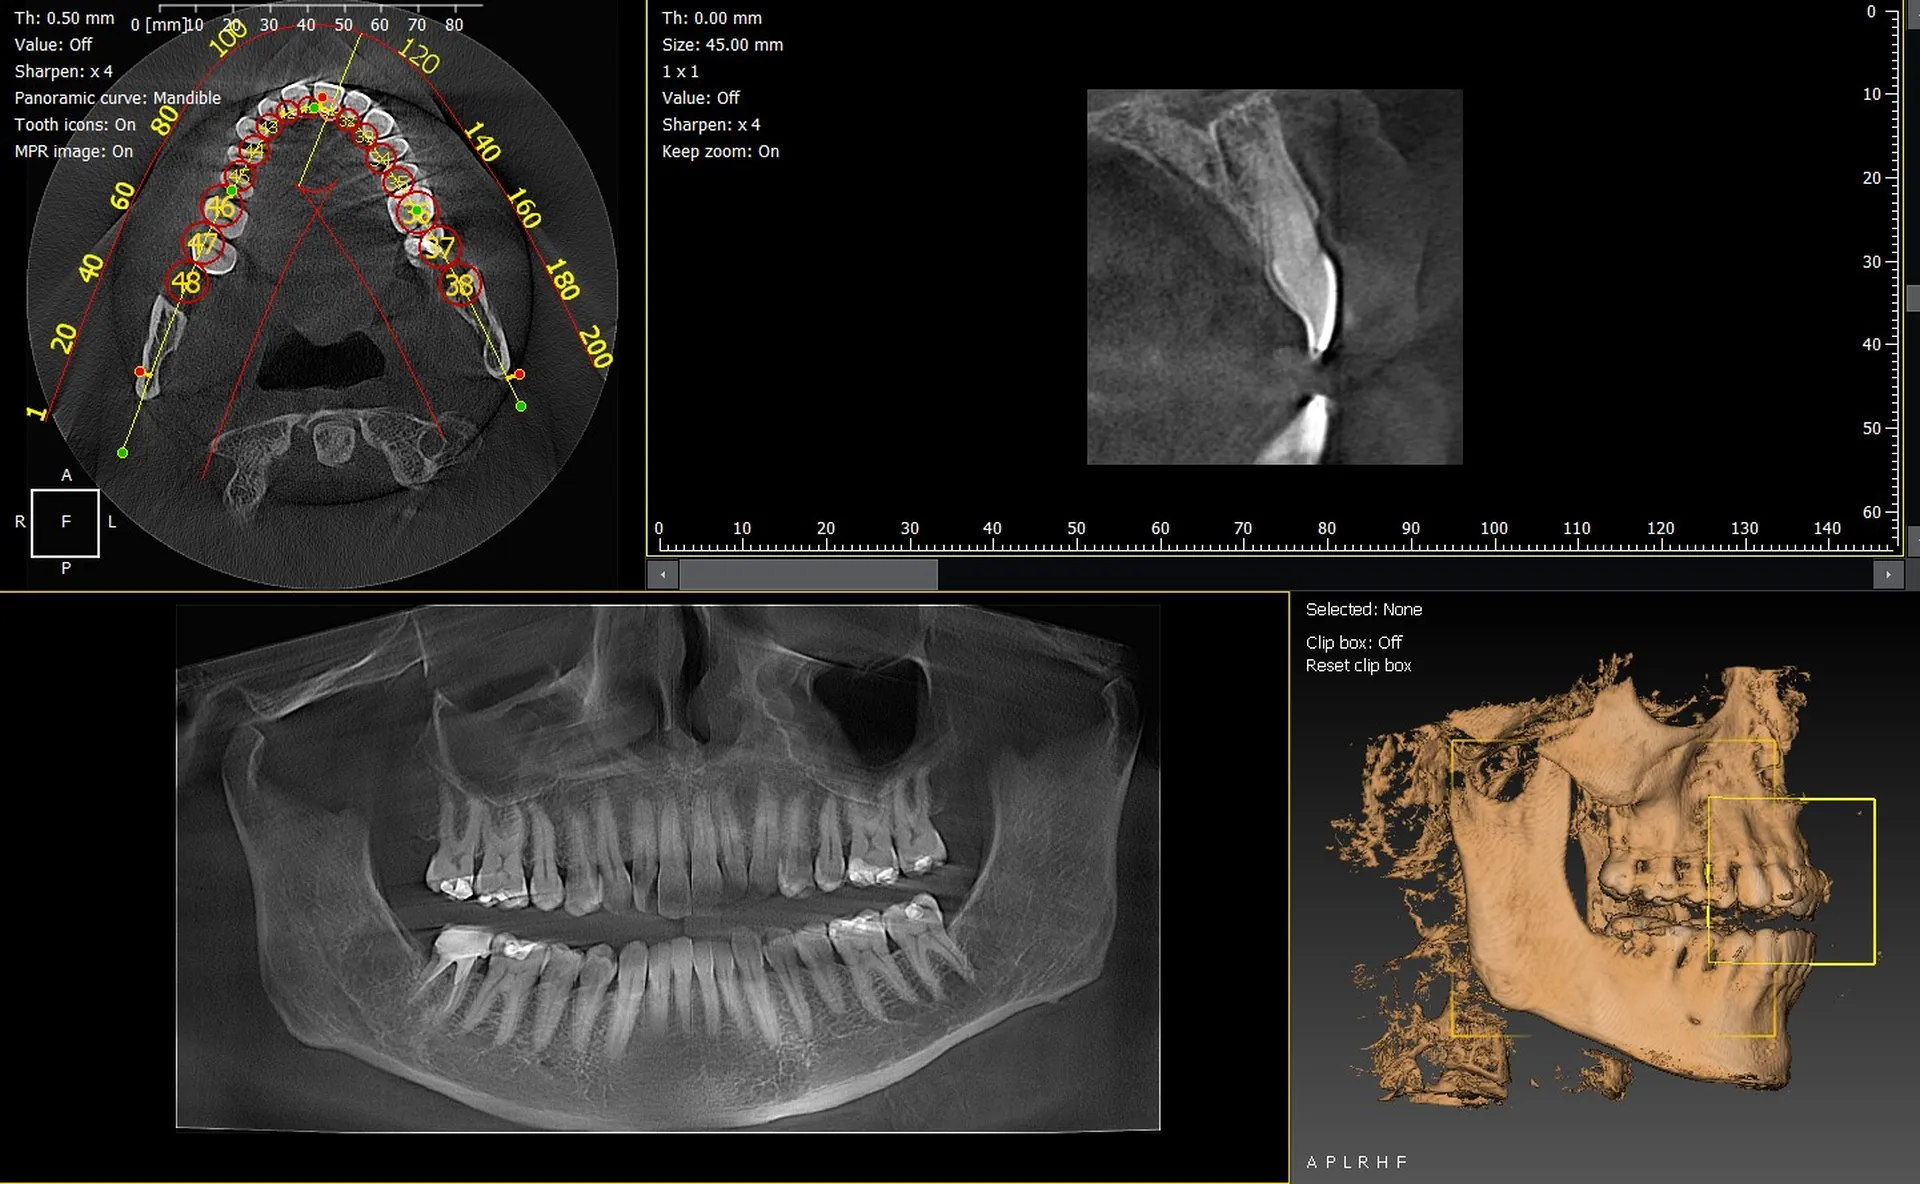

Les cabinets dentaires de Grasse et des Alpes-Maritimes (06) recherchent des solutions d’imagerie 3D fiables, modernes et adaptées à une activité clinique exigeante. Les panoramiques CBCT 3D VistaVox de Dürr Dental et l’Owandy I-Max 3D s’imposent aujourd’hui comme des équipements de référence pour obtenir des diagnostics précis et améliorer la prise en charge des patients.

VistaVox 3D : un volume adapté à l’arcade dentaire

Le VistaVox offre un champ d’exploration optimisé, idéal pour :

• l’implantologie,

• l’endodontie avancée,

• l’analyse des ATM,

• le diagnostic préchirurgical.

Son positionnement simple et son excellente résolution d’image permettent un flux de travail fluide au quotidien.

Owandy I-Max : un appareil compact et polyvalent

L’I-Max 3D séduit particulièrement les cabinets urbains grâce à :

• son format mural peu encombrant,

• des protocoles 2D et 3D complets,

• une interface intuitive,

• une installation rapide.

C’est une solution idéale pour moderniser un cabinet dentaire à Grasse sans engager de lourds travaux.